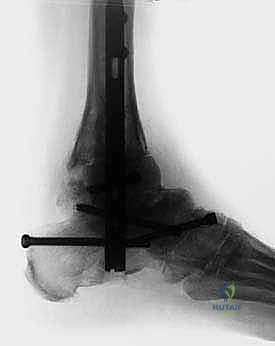

4. إدخال المسمار النخاعي

يتم عمل شق صغير أسفل الكعب. يتم إدخال سلك توجيهي، يتبعه إدخال المسمار النخاعي القوي المصنوع من التيتانيوم. يخترق المسمار عظمة الكعب، ثم يمر عبر عظمة الكاحل، ليستقر أخيراً داخل القناة النخاعية لعظمة الساق.

5. التثبيت بالبراغي القفلية (Locking Screws)

لضمان عدم تحرك المسمار أو دوران العظام حوله، يتم تثبيت المسمار ببراغي عرضية تخترق العظام والمسمار معاً من الأعلى (في الساق) ومن الأسفل (في الكعب والكاحل). يتم استخدام جهاز التصوير الإشعاعي (C-arm) داخل غرفة العمليات للتأكد من الموضع المثالي لكل مسمار.